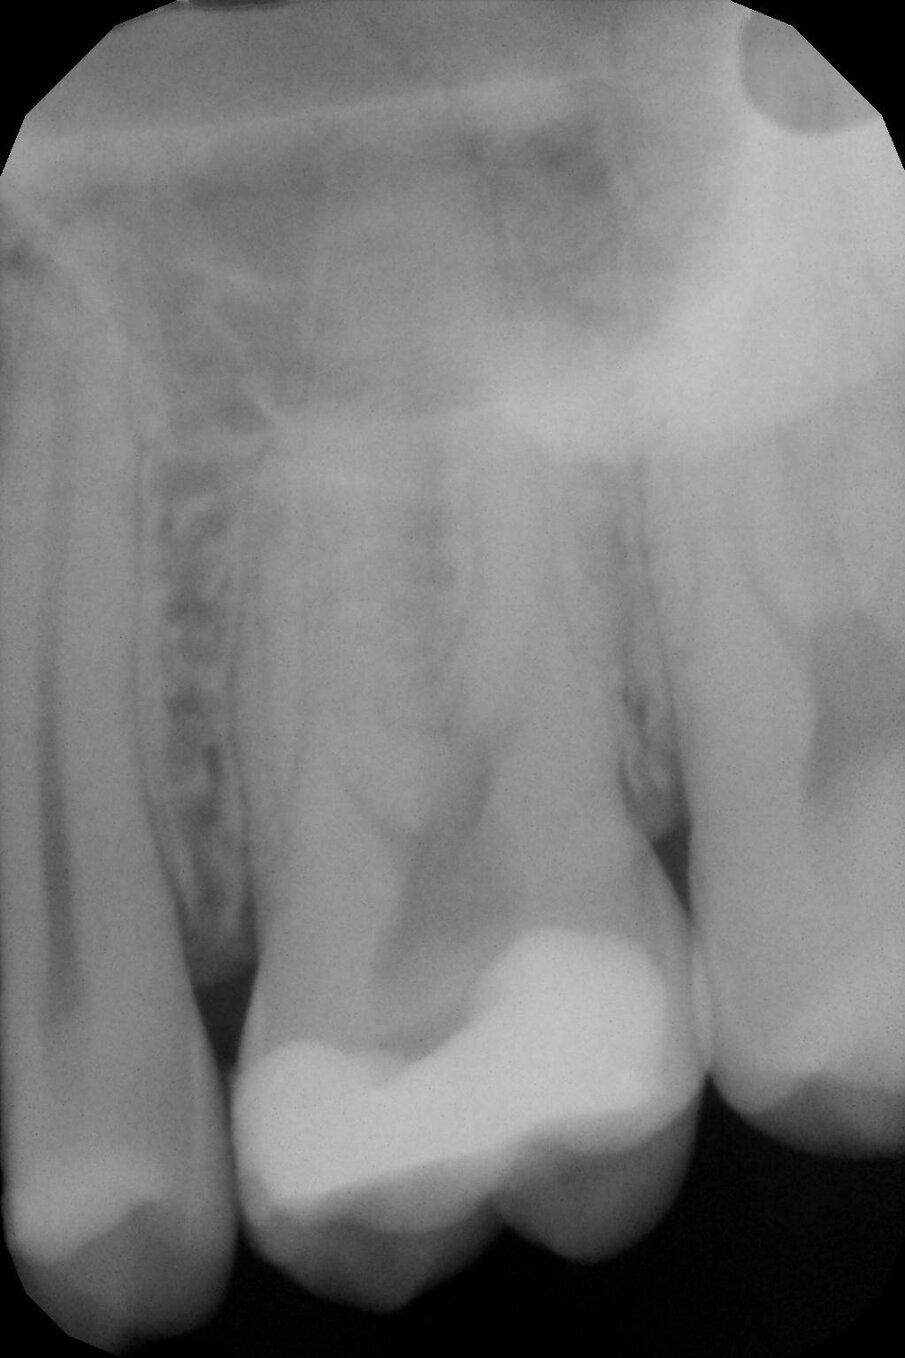

Un paziente di anni 45 giunge in urgenza lamentando un forte dolore in corrispondenza dell’emiarcata mascellare di destra. L’esame anamnestico rivela che il dolore è di tipo pulsante ed è soprattutto notturno. L’esame clinico evidenzia la presenza di un grosso restauro in composito, che era stato effettuato circa 5 anni prima, a livello dell’elemento dentario 2.6; il restauro è infiltrato occlusalmente in più punti. L’elemento in questione risulta dolente alla masticazione; il test di vitalità al freddo esacerba un dolore acuto e prolungato scatenando la sintomatologia lamentata dal paziente. L’esame radiografico di tipo periapicale (Fig. 1) conferma la presenza di infiltrazione cariosa sul fondo della cavità; non evidenzia la presenza di visibili alterazioni a livello del periapice. Viene fatta diagnosi di pulpite acuta e il piano terapeutico prevede il trattamento endodontico ortogrado.

Grazie alla radiografia periapicale possiamo effettuare una corretta valutazione preliminare dell’anatomia endodontica. Questa viene effettuata analizzando i dettagli dell’anatomia esterna e interna radicolare; così facendo possiamo intercettare immediatamente qualsiasi difficoltà che potremmo incontrare nel corso del trattamento e scegliere la migliore strategia operativa in funzione della nostra anatomia endodontica. Le radici mesio-vestibolare (MV) e disto-vestibolare (DV) sembrano abbastanza curve apicalmente e probabilmente ci aspettiamo di trovare anche il secondo canale mesio-vestibolare (Mb2) nella radice MV; la radice palatale (P) appare lunga e dritta. Visto il grado di compromissione dell’elemento dentale e l’anatomia delle radici vestibolari optiamo di scegliere degli strumenti a conicità ridotte realizzati con una lega trattata termicamente (che sposi sia le caratteristiche della martensite che dell’austenite) al fine di ottenere la massima salvaguardia della struttura radicolare residua mantenendo un ottima resistenza agli stress torsionali.

Fig. 1 - Rx periapicale preoperatoria del 2.6.

Fig.4 - Rx-periapicale di controllo post-operatoria.